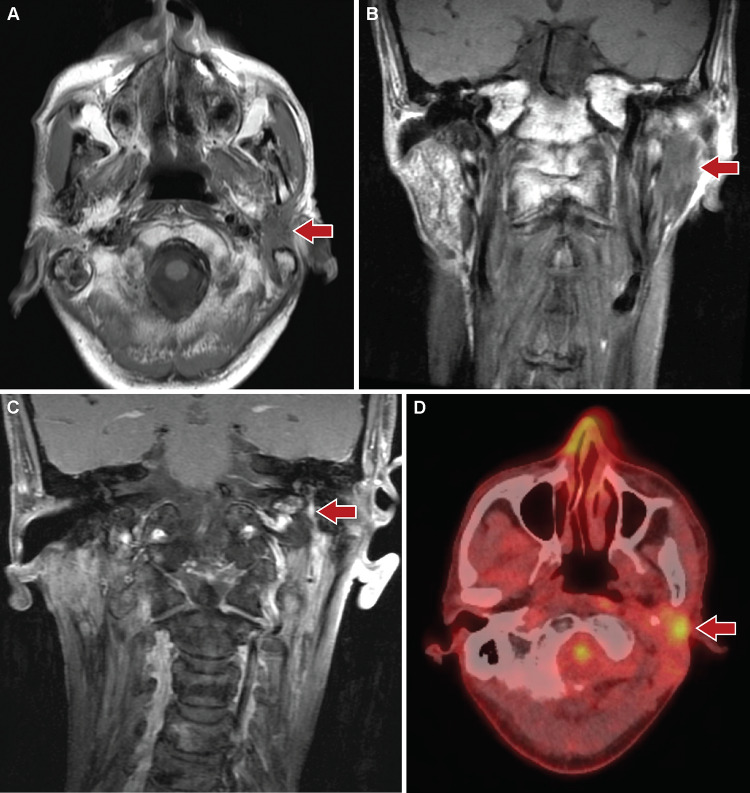

MRI of the head and neck at presentation to our hospital revealed enhancing infiltrative soft tissue thickening involving the deep and superficial lobes of the left parotid gland and extending to the left stylomastoid foramen and facial nerve (Fig. 1a-c). The findings were considered indeterminate, as the features may be seen with delayed post-radiation changes, infectious/ inflammatory changes, or malignancy. Further evaluation by positron emission tomography/ computed tomography (PET/CT) showed the left parotid lesion to be hypermetabolic (Fig. 1d). The lesion measured approximately 2.6 × 1.8 × 3.6 cm in size (anteroposterior by transverse by craniocaudal). Subsequent fine needle aspiration specimen from the left parotid was suspicious for a basaloid neoplasm; however, interpretation was limited by hypocellularity of the sample.

Fig. 1.

Radiologic findings of the parotid tumor